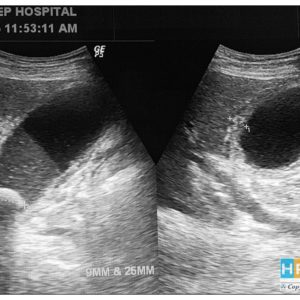

Viêm túi mật cấp